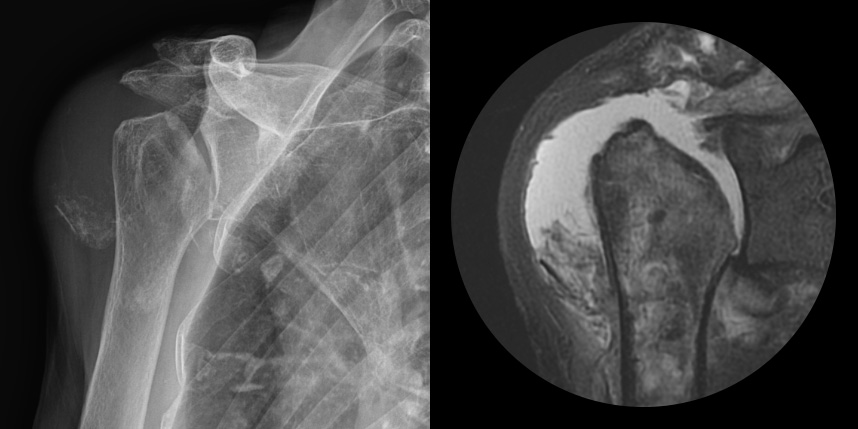

어깨 퇴행성은 많이 써서 닳고 노화에 따른 변화가 생긴 것으로, 말 그대로 어깨가 많이 사용되면서 연골이 닳아서

마모돼어 생기는 관절염입니다. 어깨 회전근개 관절병증 원인으로는 어깨 힘줄 파열을 방치했을 때 관절이 틀어진 상태에서 계속

사용하게 되면 관절이 많이 상해서 관절염까지 진행되며, 이런 경우 회전근개파열의 결과로 생긴 관절병이라고 합니다.

최근에 퇴행성 관절염, 류마티스 관절염 이외에도 많은 환자가 발생하고 있습니다.

관절내시경

비수술 치료에도 호전이 없는 경도의 관절염에서 시행합니다.